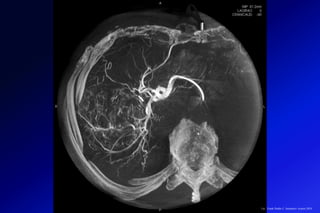

La RM CARDIACA ha evolucionado hasta convertirse en una modalidad diagnóstica

esencial en la evaluación de la miocardiopatía, gracias a su capacidad para

caracterizar la estructura y la función del miocardio. En los últimos años ha

aumentado el interés en el potencial de las técnicas de mapeo que aportan una

cuantificación directa y objetiva de las propiedades del miocardio.

Imágenes de resonancia magnética cardíaca

integral de un niño de 14 años con miocarditis

aguda. Fue hospitalizado después de cuatro

días de dolor precordial. El edema miocárdico

regional de pared media del tabique

interventricular y el edema epicárdico de las

paredes anterior, lateral e inferior se muestran

en las imágenes de cine e imágenes

ponderadas en T2. También se encontró

fibrosis / necrosis miocárdica regional en la

misma ubicación en la imagen LGE. En las

imágenes de mapeo T1, T2 y ECV, la línea de

puntos muestra el retorno de la inversión del

miocardio de "apariencia normal", excluyendo

el miocardio con edema visible o fibrosis en la

IRM convencional.